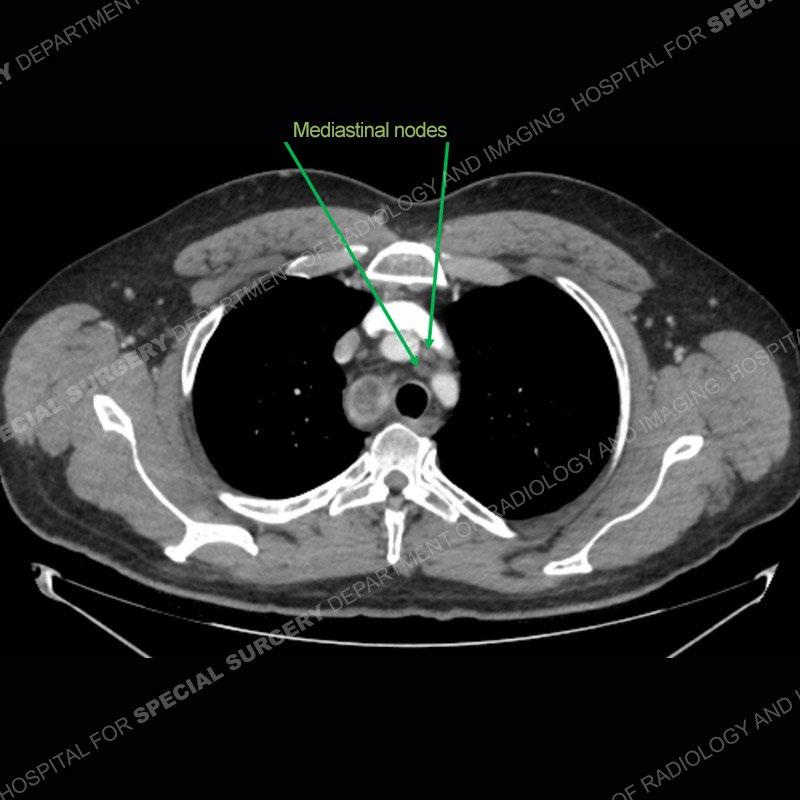

The chest radiographs demonstrate a leftward deviation of the trachea. CT images demonstrate a large, somewhat heterogeneous mass of the thyroid that extends outside the confines of the thyroid tissue. There is a subtle, enhancing soft tissue mass of the proximal right humerus. Slightly prominent mediastinal lymph nodes are present with additionally, multiple supraclavicular lymph nodes.

Although not strictly a part of the evaluation of an “incidental” thyroid lesion, evaluation of the adjacent lymph nodes and bony structures can also be quite important. In this case, there is an enhancing mass of the right humerus. This is very subtle and can only really be recognized by evaluating the density of the bone. Typicaly marrow will have a fatty density or nearly fluid density. As the density, as in this case, approaches soft tissue an infiltrative process must be entertained. Thyroid mets are markedly vascular accounting for the areas of enhancement of the humeral mass. The mediastinal and supraclavicular lymph nodes although not individually enlarged, should raise suspicion of an underlying inflammatory/neoplastic process.